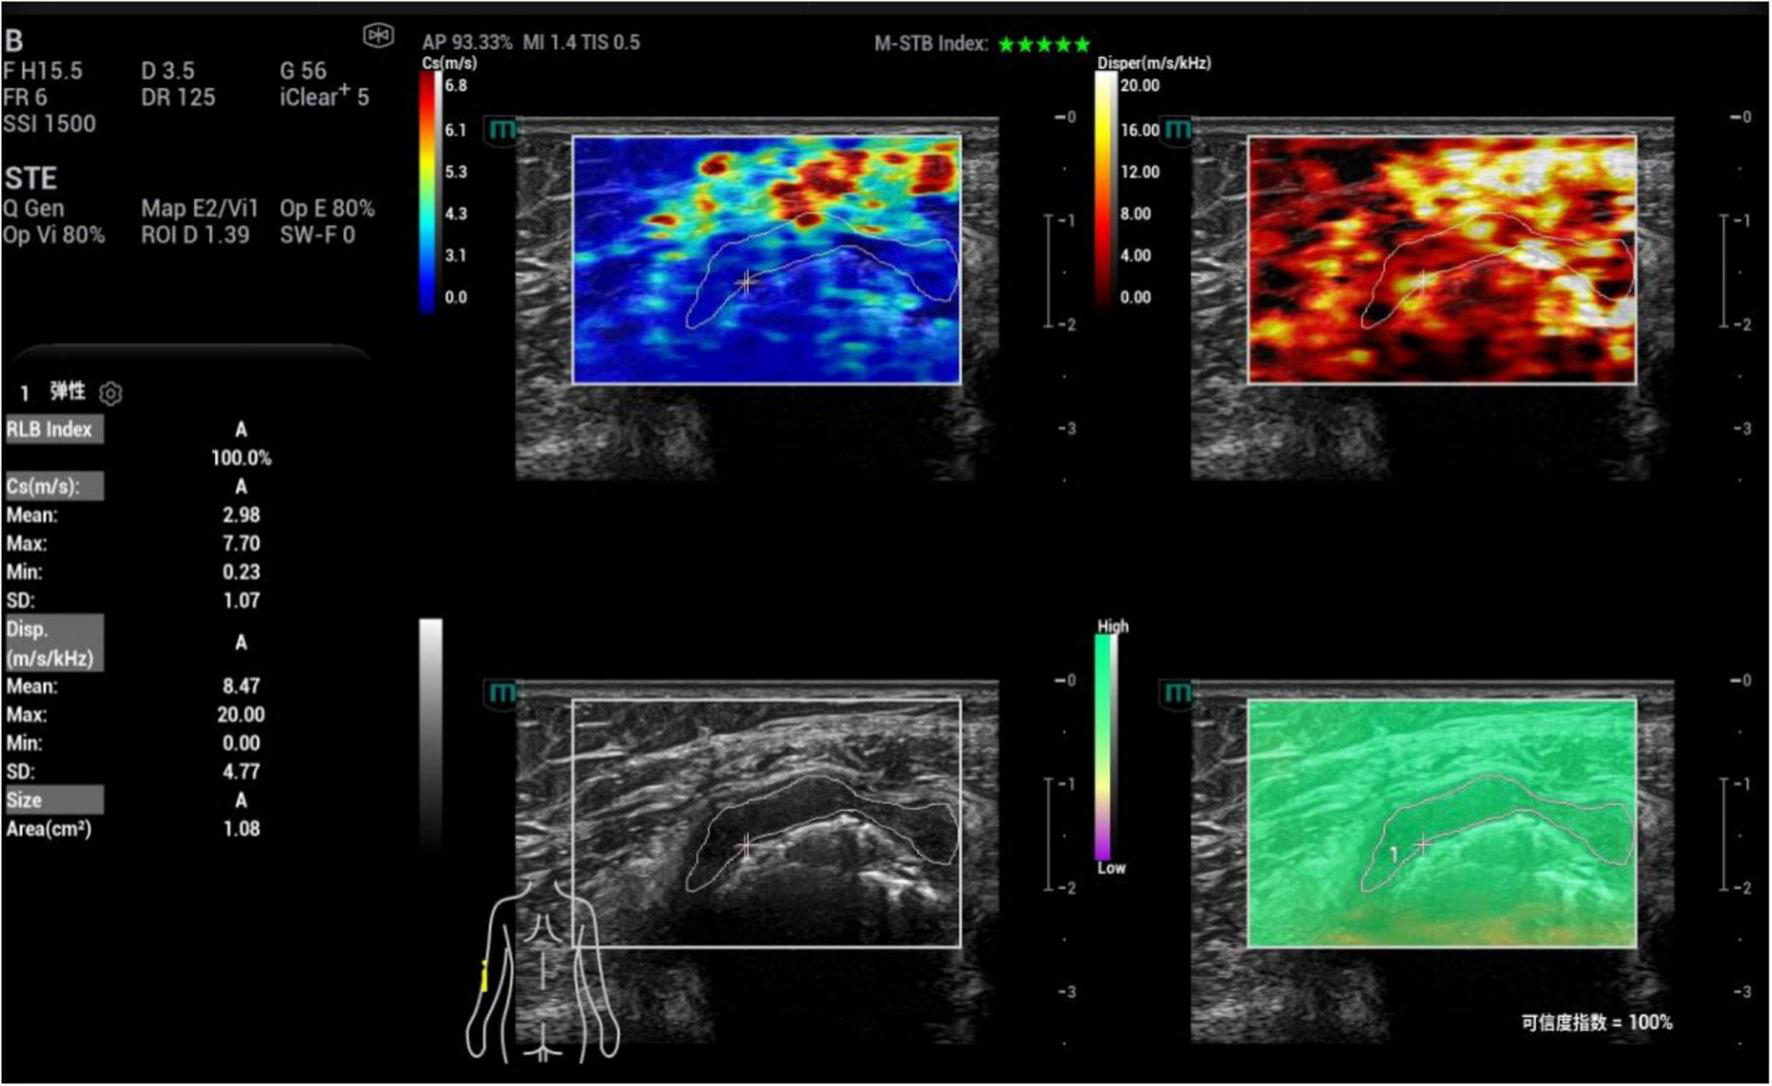

FIGURE 4

Ultrasound viscoelastic image of the left elbow joint in a patient with acute gout (AG). A 69-year-old male patient. Ultrasound viscoelastic imaging showed that the thickened synovium of the left elbow joint had a Cmean of 2.98 m/s (>cut-off value of 2.36 m/s) and a Dmean of 8.47 (m/s)/kHz [>cutoff value of 4.35 (m/s)/kHz].

Images were analyzed under the four-panel mode of viscoelastic imaging (Figures 2, 3). On the gray-scale ultrasound image, region of interest (ROI) was delineated along the edge of the thickened synovial, and the corresponding ROI was synchronously displayed on the shear wave elasticity and viscosity images. The system automatically acquired quantitative parameters: shear wave elastic parameters (reflecting tissue stiffness) including the mean, maximum, minimum, and standard deviation of shear wave velocity (C, m/s); viscosity imaging parameters (reflecting tissue viscosity) including the mean, maximum, minimum, and standard deviation of viscosity coefficient (V, Pa⋅s) and dispersion coefficient [D, (m/s)/kHz]. A total of 12 parameters were obtained. Image acquisition and data measurement were repeated 5 times, and the mean values were recorded and calculated.

Subsequently, based on gray-scale ultrasound, the maximum longitudinal section of synovial thickening in the joint was obtained for ultrasonic shear wave viscoelastography examination. When acquiring images, the probe was gently placed in contact with the patient’s skin, and stabilized with minimal pressure. The acquisition frame covered the entire lesion area. To reduce interference from respiratory movement, patients were instructed to remain calm and hold their breath for 3–5 s. Then, the viscoelastic examination was activated to enter the four-panel mode, which simultaneously displayed the gray-scale image, shear wave elasticity images, viscosity images and reliability map (RLB) (Figure 2). The system integrated quality control modes including motion stability index (M-STB) and RLB to improve data stability and reliability. M-STB was graded on a scale of 1–5 stars, which dynamically evaluated motion interference between the biomedical sensor and the subject’s skin. Images were considered to be acquired under stable conditions when M-STB ≥ 4 stars. The RLB displayed areas with high reliability in green and areas with low reliability in purple. The RLB index indicated the reliability of the image as a percentage, and images were deemed qualified when the RLB index > 90%. All physicians performing ultrasound examinations and parameter analysis were completely blinded to the patients’ clinical information and did not refer to any clinical data during the operation, including demographic characteristics, medical history, laboratory results, joint aspiration findings, clinical diagnoses, and treatment plans.